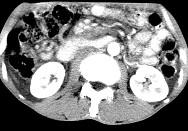

问题 女,50岁,中上腹疼痛,消瘦乏力,影像检查如下图,最佳的诊断是()

选项 A.慢性胰腺炎 B.急性胰腺炎 C.胰腺癌并腹膜后淋巴结转移 D.胰岛素瘤 E.腹膜后淋巴瘤

答案 C